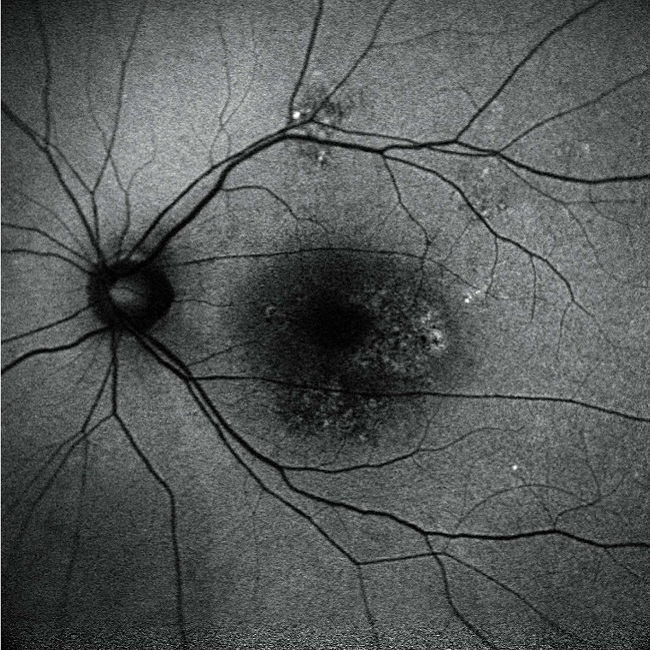

・眼底自発蛍光

2つの波長で網膜色素上皮における自発蛍光(造影剤を使わない)を発するリポフスチン(老廃物)を観察し網膜色素上皮の非侵襲で検査できます。主な対象疾患は、加齢黄斑変性、網膜色素変性症などです。